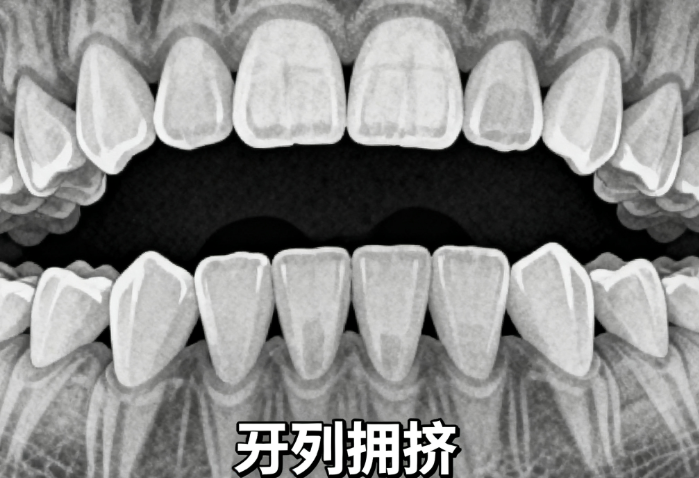

综上所述,河北金属牙套一般多少钱?根据目前的市场情况,普通金属牙套价格通常在3000元至5000元之间,国产与进口差价近3000元,不同品牌价格差异也较大。如果你是青少年,矫正价格可能在3000元至5000元之间;如果是成人,价格可能在5000元至8000元之间。建议你提前预约免费检查,了解自己的牙齿情况,并多对比几家医院,确保价格合理、服务到位。记住,价格不是只有这一个的参考,选择合适的医生和方案才是关键。